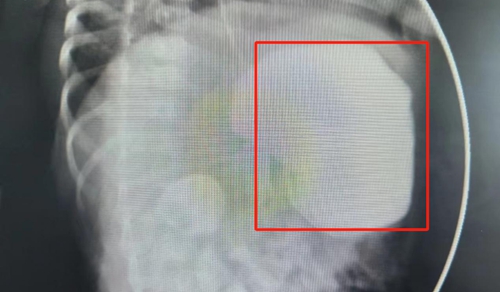

造影檢查

△由于梗阻,造影劑堆積在胃部下不去